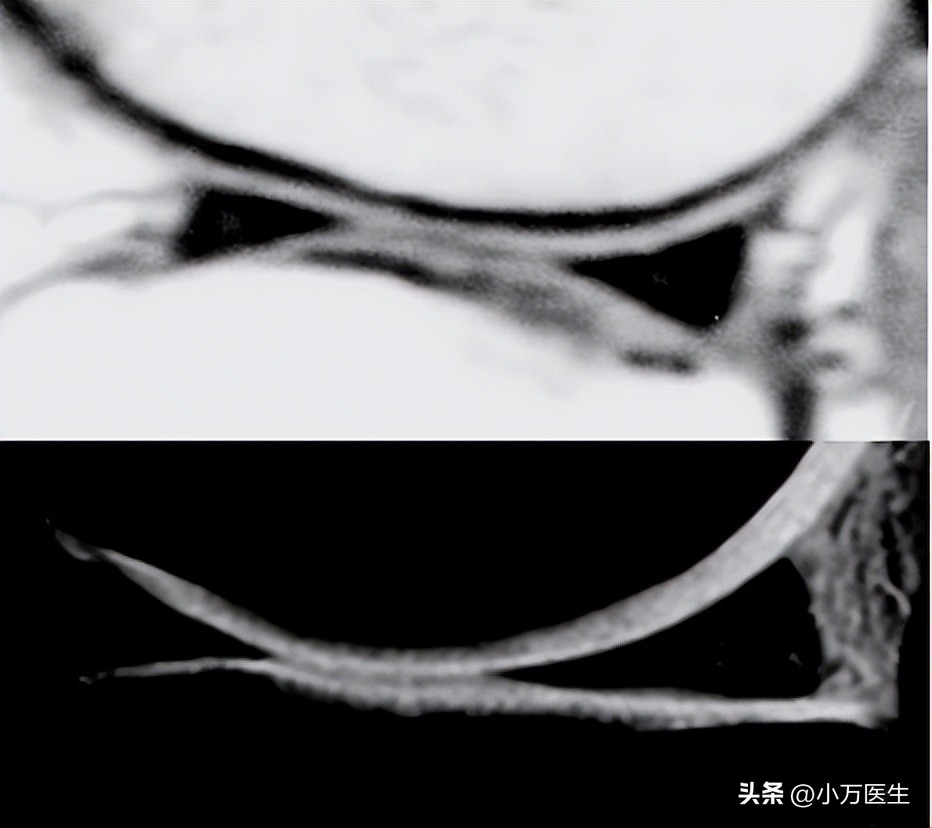

外侧半月板后角可发出两根韧带,分别走行于后交叉韧带前、后方,走行前方的称为Humphery’s韧带,走行后方的是Wrisberg’s韧带。正常人群中36%具有Humphery’s韧带,60%~ 70%具有Wrisberg’s韧带,约4%两者皆有。

(1、Wrisberg’s韧带;2、Humphery’s韧带)